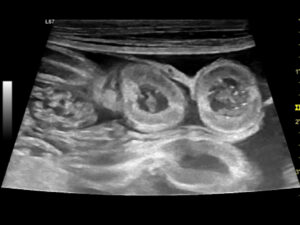

La ecografía abdominal es de gran ayuda, ya que la presencia de engrosamiento de la mucosa intestinal es frecuente en EII y linfoma intestinal difuso, mientras que la aparición de estriaciones hiperecogénicas en la mucosa se relaciona con la presencia de linfangiectasia en más del 90 % de los casos10 (imagen 2).

Imagen 2. A y B) Ecografías de un bulldog francés de 8 años con signos clínicos compatibles con EPP, en las que se aprecian estriaciones hiperecogénicas en la mucosa, que en la mayoría de los casos se corresponden con linfangiectasias, que posteriormente se confirmaron mediante histopatología. C) Ecografía de una perra mestiza con hipoalbuminemia grave asociada a una enteropatía inflamatoria. Puede apreciarse una hiperecogenicidad marcada y difusa de la mucosa intestinal, así como la presencia de efusión abdominal.